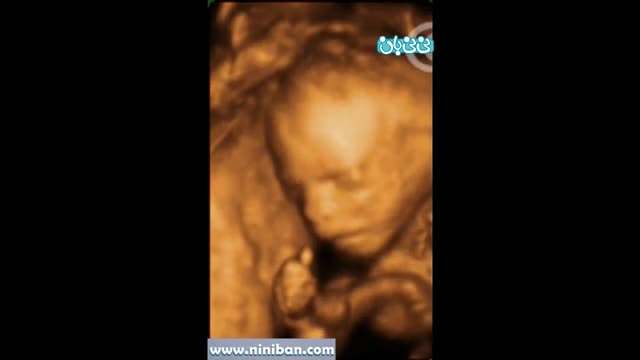

سونوگرافی چهار بعدی در بارداری هفته بیستم